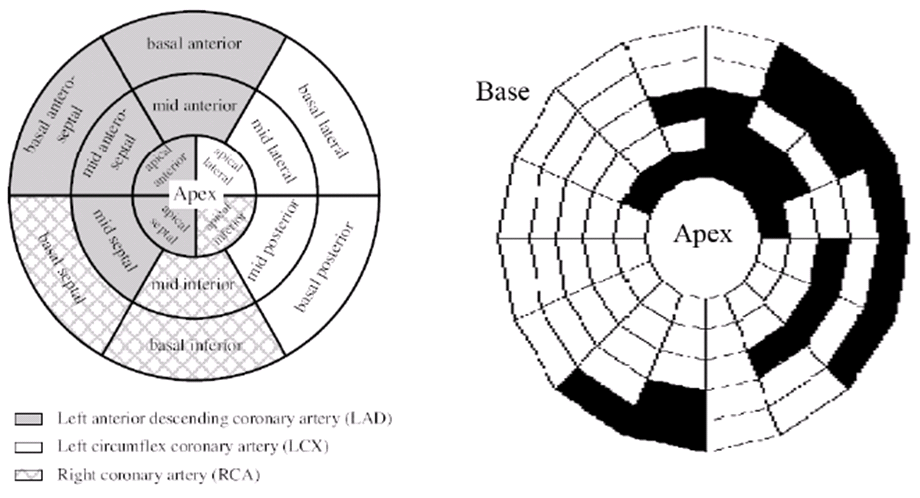

Fig. 11 shows the approximate infarct localization for the MI subject based on the comparison between normal and MI subjects’ effective strain during the cardiac cycle. Since the circulatory system of heart is determined very well, it is possible to make reliable conclusions about the problem that caused MI based on expert diagnosis and using these comparisons.